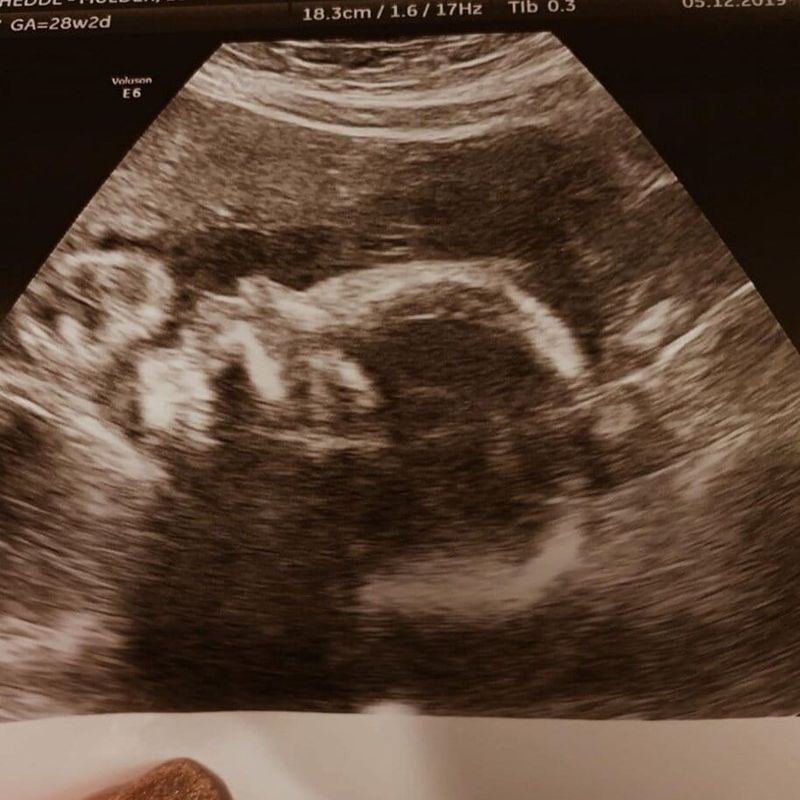

A las 23:30 llegamos al hospital Maxima y me llevaron a las suites de maternidad. Aquí finalmente recibimos la explicación que tanto buscábamos. A nuestra niña le dieron maduración pulmonar porque pensaron que yo tenía una hernia intestinal (intestino torcido). Podría necesitar someterme a una cirugía. También nos hablaron del NICU, que nuestra niña era fuerte y estaba increíblemente bien. Me pusieron un suero intravenoso. Durante la noche, nos preguntaron si podían traer a nuestro otro hijo y si podían reservar la casa Ronald McDonald para nosotros. El primer día en Eindhoven consistió en doctores, enfermeras y dietistas. Cada vez que comía algo, me dolía el estómago. Debido a esto, cambiamos a una dieta líquida. Uf, qué pesadilla. Todo este tiempo, nuestra niña estaba increíblemente bien. Los médicos querían hacer una resonancia magnética. No había pasado ni media hora desde que volví a la habitación cuando se abrió la puerta: 'Vamos a operarte hoy.' Estábamos muy asustados porque había una (pequeña) posibilidad de que nuestra niña naciera antes de las 26 semanas.

La cirugía salió bien. Ya llevaba más de cuatro horas tumbada en el CTG. Tenía contracciones fuertes, pero afortunadamente sin dilatación. Al día siguiente, las contracciones se volvieron bastante regulares y dolorosas. Cada hora medían mi cuello uterino. De nuevo, sin dilatación. Al día siguiente, las contracciones eran aún más dolorosas y también sentía dolor de parto en la espalda. En el CTG, se veían claramente. Estaba resoplando como loca y cada vez más asustada. El latido del bebé fluctuaba salvajemente: pasaba de muy alto a bajo y viceversa. Pensamos: "¡Esto es! ¡Van a sacarla!" Después de unas horas, las contracciones parecían disminuir. El ginecólogo nos dijo que no iban a sacar al bebé, porque todavía se veía bien. Me permitieron irme a casa con mucho descanso.

Actualmente estoy embarazada de 27 semanas y 2 días, y nuestra pequeña niña todavía está agradable y cálida dentro de mí. Aunque los doctores son muy positivos y no anticipan un parto prematuro próximamente, mi miedo aún no ha disminuido completamente.